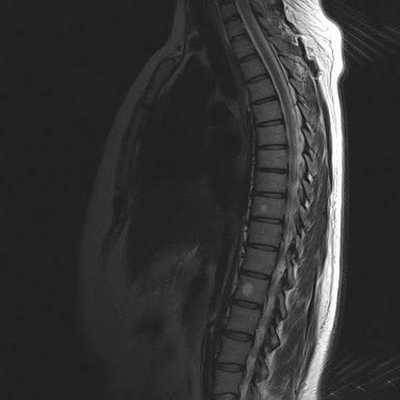

В результате томографии врач получает серию послойных изображений спины, выполненных в аксиальной, сагиттальной и фронтальной проекциях. На основании полученных фото возможно построение 3D-модели изучаемой зоны.

Гемангиомы на МРТ снимке грудного отдела позвоночника (сагиттальная проекция, Т2 взвешенное изображение)

МРТ снимок грудного отдела позвоночника в сагиттальной проекции, Т1 взвешенное изображение

МРТ грудного отдела в сагиттальной проекции, линии разделяют позвонки Th1-12